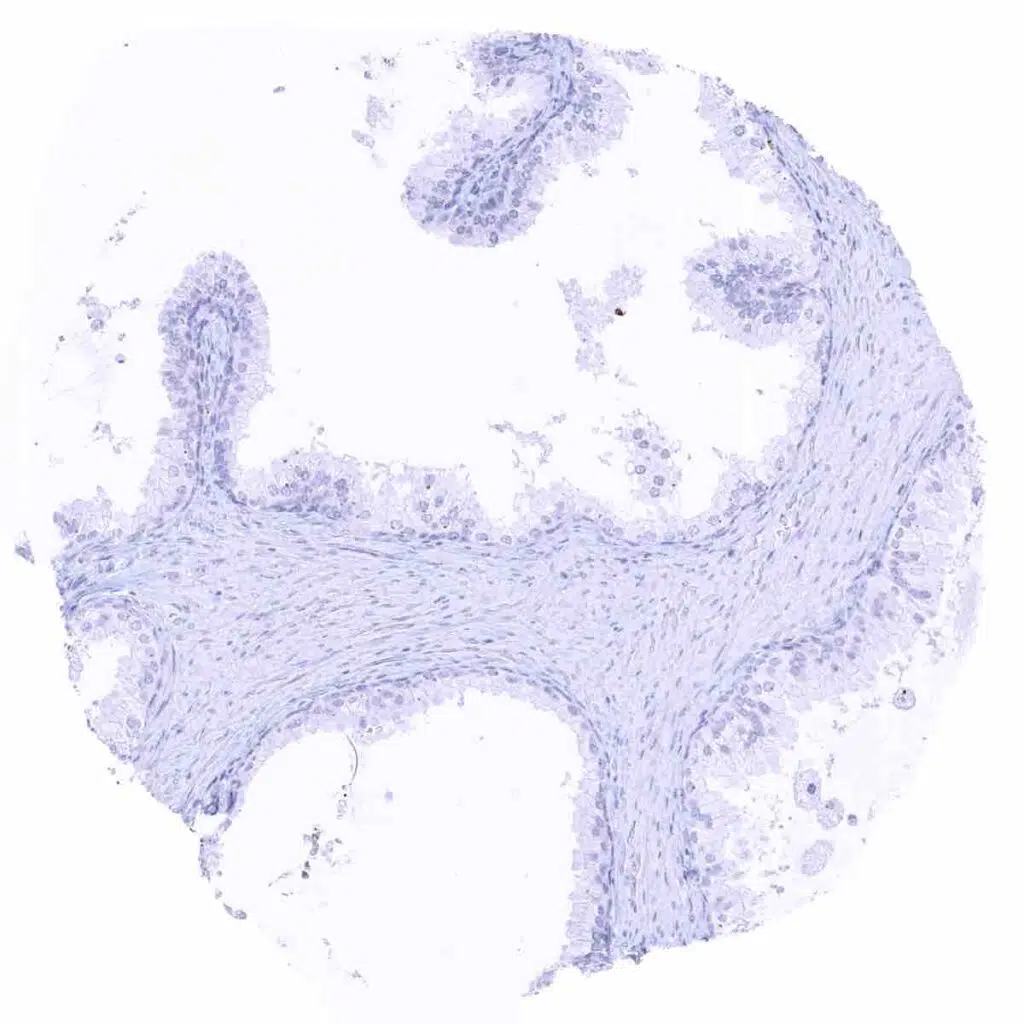

Uterus, endocervix